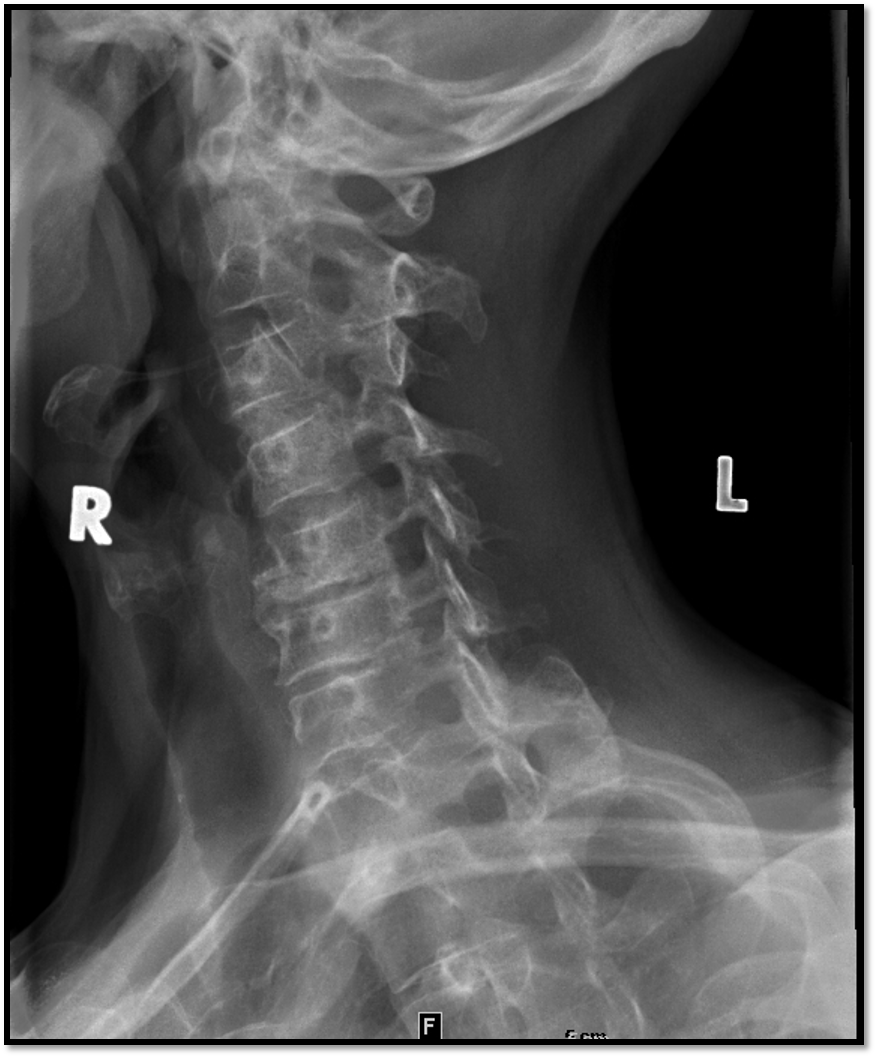

Lateral Cspine Criteria

A

• SI’d articular pillars and open zygopophyseal joints

• superimposition of posterior vertebral bodies

• mandible off spine

• open intervertebral spaces

• rotation issue: posterior borders arent aligned

• tilt issues: double lines at zygo joints

• need to do swimmers: cant see C7 and T1